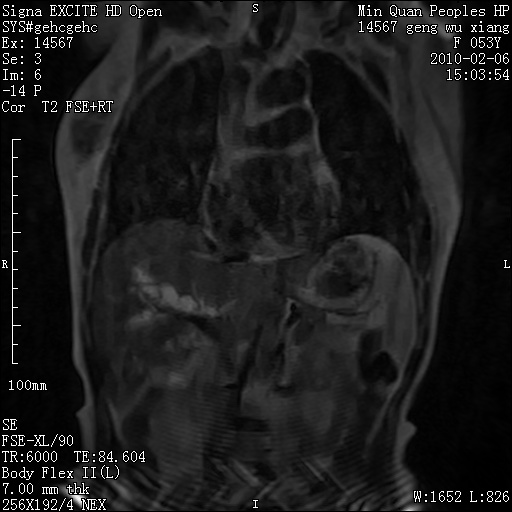

标题: MRI2762:胆道梗阻原因?

f,53y,全身黄染多日。

高位胆道梗阻 胆管癌可能性大

支持 高位胆道梗阻 胆管癌可能性大。